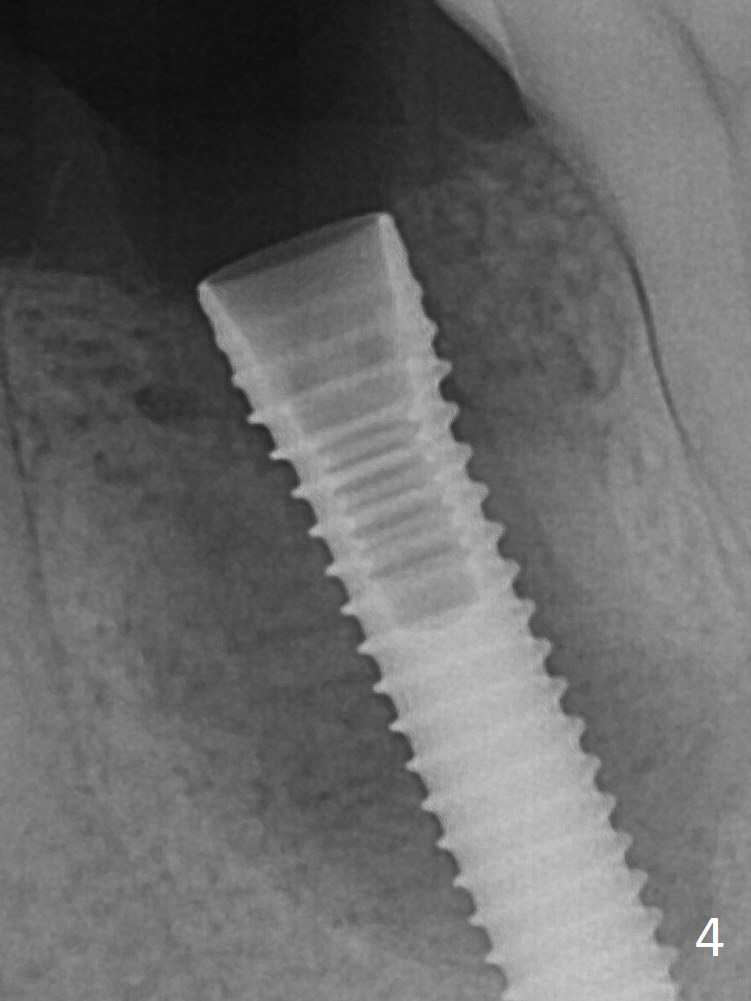

It appears that a 3.8x18 mm  implant is not placed deep enough.  Following 3-4 more turns of the implant and placement of a 5.5x4(3) mm abutment (Fig.5 A), allograft is placed (*).  The bone around the implant appears to have regenerated 4 months postop (Fig.7).